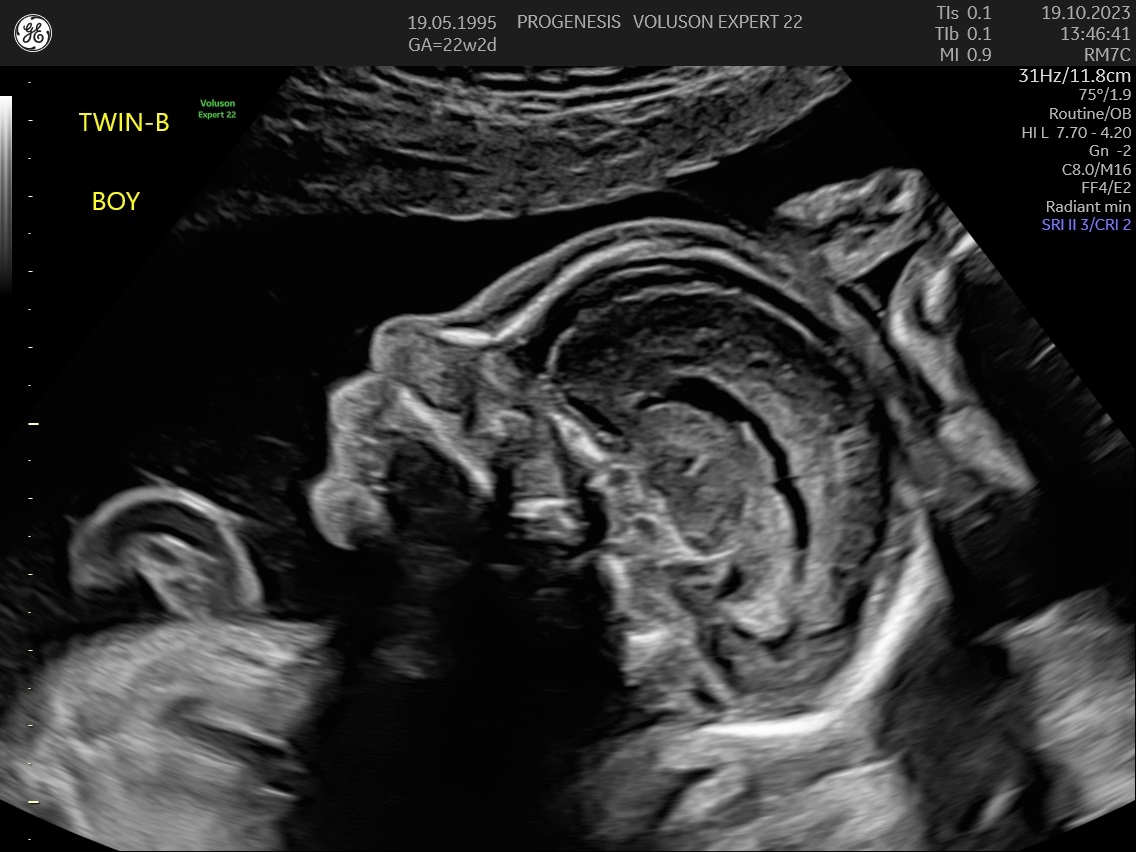

α) Η λεπτομερής αξιολόγηση της εμβρυϊκής ανατομίας, όπου αναγνωρίζονται τυχόν ανατομικές ανωμαλίες.

γ) Ο έλεγχος της ανάπτυξης του εμβρύου, του πλακούντα, του ομφαλίου λώρου και του αμνιακού υγρού.